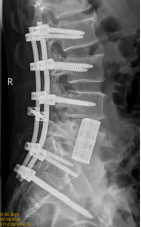

7. 复杂脊柱骨折内固定技术

随着区域内社会经济开发,复杂严重脊柱脊髓损伤病例增加,如何良好的手术治疗解除脊髓压迫、重建脊柱稳定性,使患者创伤最小、收益最大是促进患者康复至关重要的一环。性爱视频

已熟练开展各类脊柱损伤修复重建技术,每年完成复杂脊柱骨折手术处于区域领先水平。